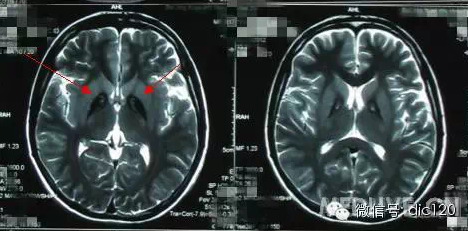

診斷小腦萎縮通常需要進(jìn)行神經(jīng)系統(tǒng)檢查、影像學(xué)檢查(如腦部CT或MRI)和實(shí)驗(yàn)室測試,治療小腦萎縮的方法主要包括藥物治療、物理治療和康復(fù)訓(xùn)練等,藥物治療旨在緩解癥狀和改善生活質(zhì)量,物理治療幫助患者恢復(fù)肌肉力量和運(yùn)動功能,康復(fù)訓(xùn)練則包括語言治療、認(rèn)知訓(xùn)練和心理支持等。